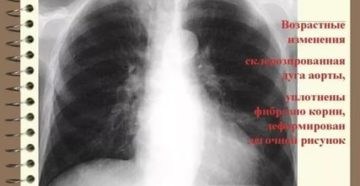

Лечение уплотнения корней легких народными средствами Период межсезонья сопровождается затяжными дождями и простудными заболеваниями. В…